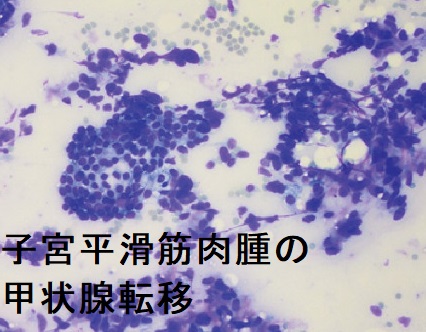

高エストロゲン血症は乳癌・子宮内膜がん(子宮体癌)の原因だが甲状腺分化癌(乳頭癌・濾胞癌)にも関与。子宮内膜がん(子宮体癌)と甲状腺癌(重複癌)・腺腫様甲状腺腫をおこす遺伝病はコーデン(Cowden)症候群、ポイツ・ジェガーズ症候群、遺伝性非ポリポーシス大腸がん(リンチ症候群)、家族性腺腫様甲状腺腫。エストロゲン受容体・プロゲストロン受容体(ER/PgR)を持つ篩(ふるい)型[モルラ(渦巻き)型]甲状腺乳頭癌も存在。子宮体部神経内分泌腫瘍は極めてまれで悪性度が高い。子宮平滑筋肉腫の甲状腺転移は非常にまれで、甲状腺原発の平滑筋肉腫と鑑別。

子宮平滑筋肉腫(uterine leiomyosarcoma:uterine sarcoma)の甲状腺転移は非常にまれです。子宮平滑筋肉腫は婦人科腫瘍の中でも特に予後不良で、早期より肺・肝臓・腎臓・脳・骨へ血行性転移します。子宮頸癌に対する根治的放射線治療など、骨盤への放射線照射との関連が強い。[Oncol Res Treat. 2018;41(11):680-686.][Int J Gynecol Pathol. 2017 Jan;36(1):31-41.]

子宮平滑筋肉腫の甲状腺転移は

- 50代女性に多い

- 全身への遠隔転移の一部分として発症

- 頸部腫大、あるいは全身の遠隔転移検索で見つかる

- 穿刺細胞診による正診率は100%、紡錘形細胞と異型細胞を認める

甲状腺未分化癌 と診断されたケースもある[Malays J Pathol. 2021 Apr;43(1):69-73.] - 気道閉塞や両側反回神経麻痺があれば甲状腺摘出手術

[Thyroid. 2007 Dec;17(12):1295-7.](Int J Gynecol Cancer 16 : 442-445, 2006)

さらに、子宮平滑筋肉腫の甲状腺転移は、甲状腺原発の平滑筋肉腫と鑑別が必要(稀中の稀、誰も知らない甲状腺平滑筋肉腫)(World J Clin Cases. 2019 Feb 26;7(4):473-481.)。

下は、子宮平滑筋肉腫の甲状腺転移 超音波(エコー)画像(内分泌甲状腺外会誌 32(3):205-210,2015)